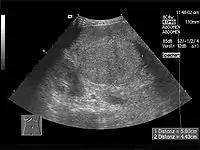

Хворим проводять ультразвукове дослідження органів черевної порожнини, при цьому оцінюють стан паренхіми печінки та судин системи ворітної вени, розміри органу. За необхідності проводять комп'ютерну рентгенівську томографію органів гепатопанкреатичної ділянки.